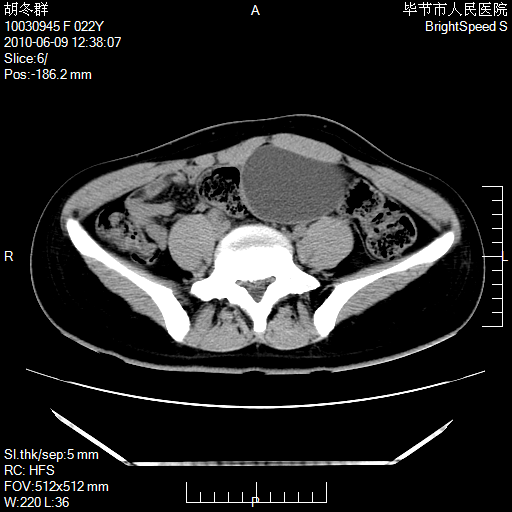

患者23岁,发现腹部包块3月。

盆腔内囊性占位;穿刺或者直接手术拿掉即可,不必紧张。

左侧卵巢囊腺瘤或囊腺癌

盆腔内囊性占位性病变;考虑左侧卵巢囊腺瘤。

有分隔、壁薄,支持考虑左侧卵巢囊腺瘤。

左侧卵巢浆液性囊腺瘤。

支持考虑左侧卵巢囊腺瘤;宫腔积液。

有分隔、壁薄,支持考虑左侧卵巢囊腺瘤。排尿后,膀胱缩小,由于重力作用,肿块下移就到了膀胱位置,很好理解。